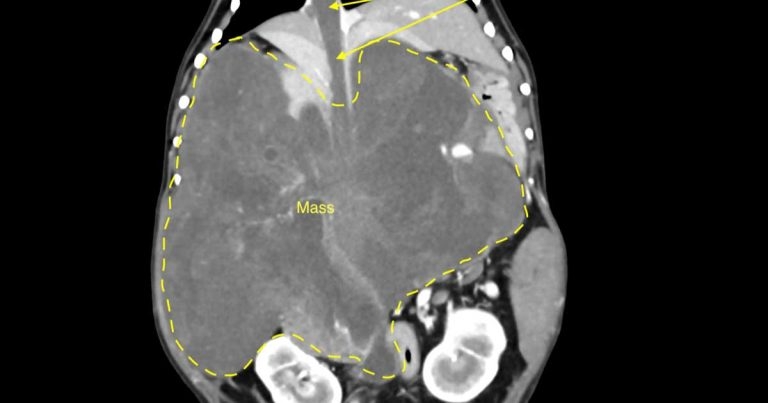

A CT scan showed the large mass within the cranial abdomen that was displacing abdominal structures, with a thrombus completely obstructing the vena cava.

The animal had lost a lot of weight and had a very distended abdomen. A CT scan showed the large mass within the cranial abdomen that was displacing abdominal structures. The mass appeared to arise from the caudate process of the liver.

A thrombus completely obstructed the vena cava – the major vein that normally returns blood to the heart from the limbs and kidneys.